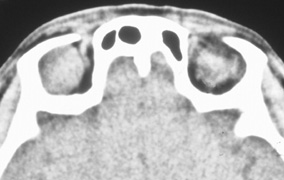

Fig. 9. A,B. Coronal and axial CT images of a large intraconal neoplasm. C. Because it was felt to represent a well-encapsulated cavernous hemangioma, this lesion was a candidate for removal via an eyelid crease orbitotomy without bone removal. The eyelid crease incision marked. D. Incision made with scalpel. E. Orbicularis muscle is tented up and incised to expose the underlying septum. F. Dissection of a skin-muscle flap deep to orbicularis exposes the orbital septum and superior orbital bony rim. G. Cutting cautery is used to incise periosteum along the superior and lateral rims; finger palpation of the bone helps to direct this incision. H. Periorbita is elevated along the mesial surface of the lateral orbital rim in order to expose the deep orbital tissues. I. The cavernous hemangioma is visualized in the wound. Retraction is provided by one or more malleable retractors. J. Cryoprobe is affixed to the hemangioma to facilitate manipulation of the lesion. K. Large cavernous hemangioma after removal through the eyelid crease incision which was accomplished without bone removal. L. Periorbita is reattached over the lateral rim. M. The eyelid crease incision is closed with a running suture.